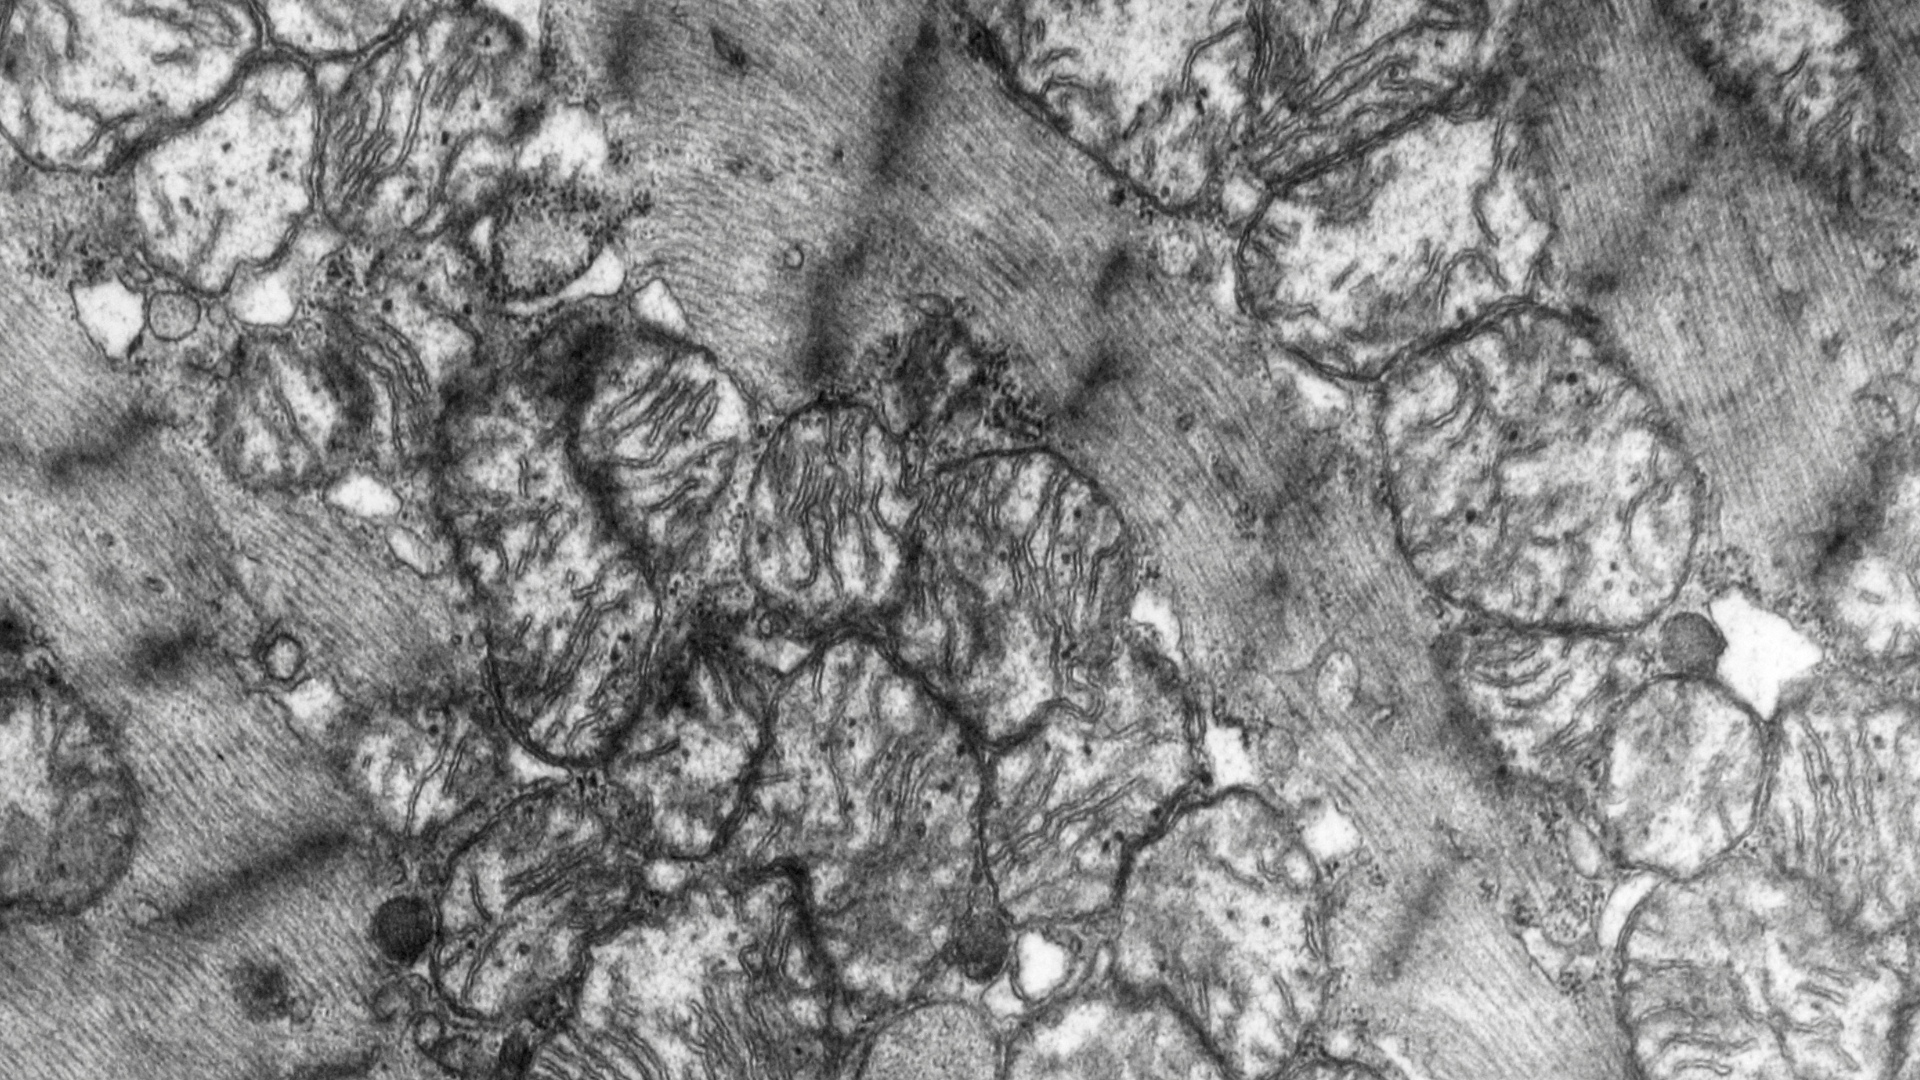

Our mighty mitochondria perform some of the most amazing aspects of health because of their ability to convert food into energy. Mitochondria are tiny, microscopic “organelles” (essentially ancient bacterium passed down from mother to child that have their own DNA, different from ours) that populate nearly every cell of our body, red blood cells being a notable exception. Their functions are critical for achieving and maintaining a well-regulated body equipped with enough energy to not only survive but to really thrive.

Mitochondria are primarily responsible for the conversion of the food we eat – carbohydrates, fats and proteins – into our body’s main energy currency, ATP (adenosine triphosphate). ATP is the fuel that makes our bodies function. The number of mitochondria that inhabit any given cell in our body depends on that cell’s energy needs. For example, there may be 1,000-2,000 mitochondria in each individual liver cell, or 5,000-8,000 in just one heart cell, or 2 million in brain cells (neurons).